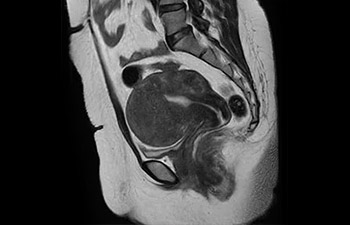

• Es una innovadora técnica de aceleración que no solo permite agilizar las secuencias, sino todo el estudio. • Implementación especial con la que las exploraciones en 2D y 3D pueden llegar a ser hasta un 50% más rápidas con una calidad de imagen prácticamente equivalente.1

• Se puede usar con todos los contrastes y con todas las regiones anatomías.

con Compressed SENSE